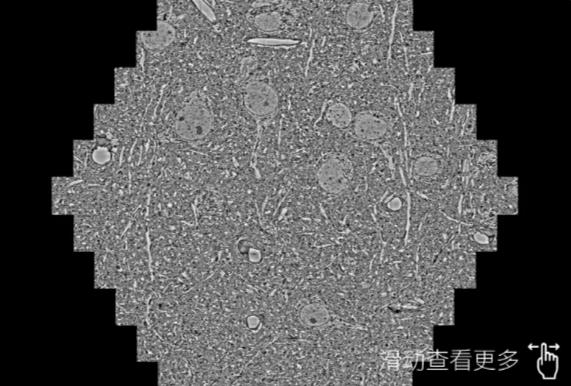

鼠脑切片。左图使用四川蔡司四川扫描电镜MultiSEM706对165μmx143pm面积区域成像,耗时仅需1.5秒。右图为鼠脑切片中30μm区域放大效果。样品由芝加哥大学B.Kasthuri提供。